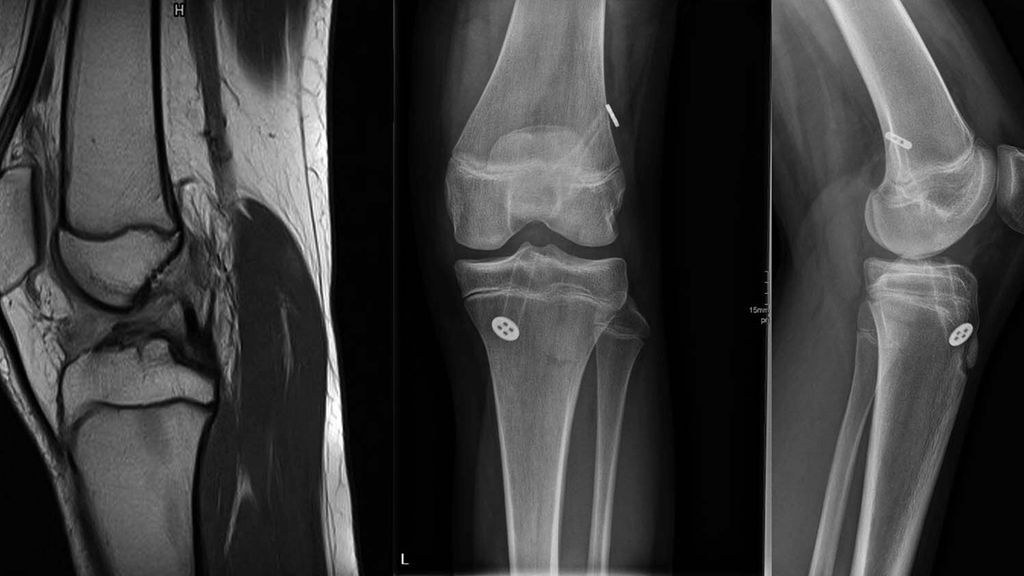

Bei den fugenkreuzenden Techniken können beide oder nur ein Kanal transepiphysär angelegt werden. Eine Verletzung der Tuberositas tibiae soll jedenfalls vermieden werden und die Epiphysenfugen sollten nicht mit Knochenblöcken oder Implantaten überbrückt werden. Bei jugendlichen Patienten kurz vor dem Wachstumsabschluss stellt die transepiphysäre VKB-Rekonstruktion ein reproduzierbares und verlässliches Verfahren dar (Abb. 3).

Abb. 3: MRT einer 13-jährigen Fußballerin mit VKB-Ruptur und postoperative Röntgenbilder nach Rekonstruktion mit autologer 4-fach-Semitendinosussehne und extrakortikaler Fixation (aus Reuter und Stotter 2022)45